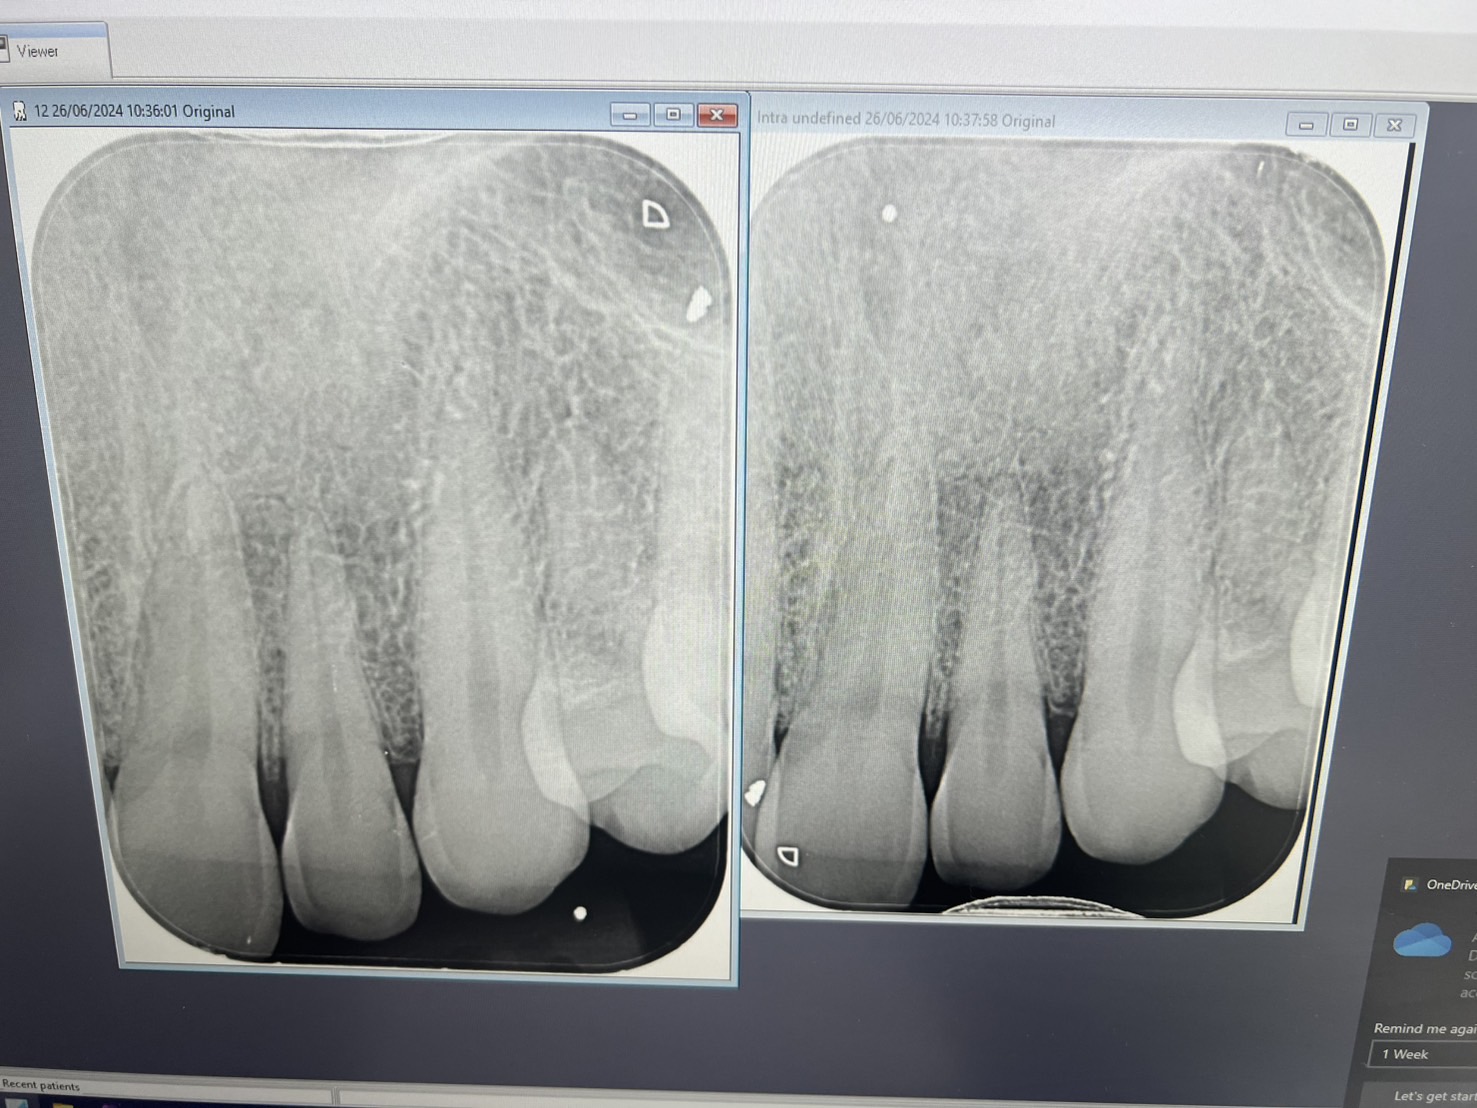

ผมมีอาการปวดบริเวณรากฟันตำแหน่งฟันตัดซี่ข้างบนซ้าย (22) ตำแหน่งที่ปวดบริเวณรากฟันตรงใต้รูจมูกข้างซ้าย แรกๆคือเป็นอ่อนๆ และไม่ได้รู้สึกปวดตลอดเวลา จึงไปหาคลินิกหมอฟันใกล้บ้าน หมอทำการ X-Ray ให้แล้วบอกว่ารากฟันปกติ หมอบอกว่าอาจจะเป็นที่เส้นประสาทอักเสบแล้วจึงแนะนำให้ทานยาบำรุงเส้นประสาท

ช่วงแรกผมยังไม่ได้ทานยาอะไรเพราะอาการยังไม่ถึงกับหนักคิดว่าอาจจะหายเองได้ แต่ผ่านมาหลายเดือนอาการเริ่มหนักขึ้น ปวดที่รากฟันจนลามไปปวดหัวด้านซ้าย (บริเวณทัดดอกไม้ด้านซ้าย) จึงไปปรึกษาหมอที่สถาบันทันตกรรม ทางคุณหมอได้ X-Ray เพิ่ม ไปจนถึงทดสอบฟันด้วยความเย็น การเคาะ ก็สรุปออกมาว่าฟันไม่ได้ผุ รากฟันไม่ได้มีปัญหา หมอแนะนำให้ทำเฝือกขบฟัน เพราะคาดว่าอาการเกิดจากการกัดฟันของผมเพราะฟันมีรอยบิ่นและร้าว ทำให้เบ้าฟันอาจจะอักเสบ

- หมอฟันบอกฟันไม่ได้ผุและรากฟันไม่มีปัญหาจากการ X-Ray